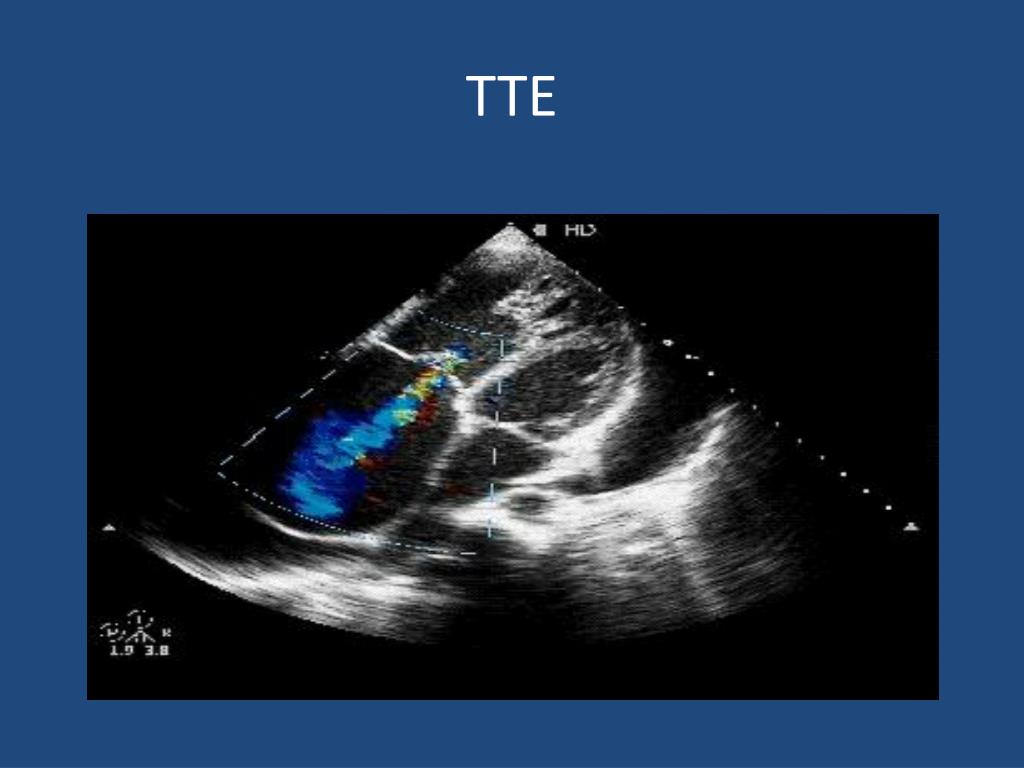

20. TTE

21. Essential preoperative info • Presence of tricuspid valve disease • Organic, functional, or mixed • Degree of regurgitation • Direction of the regurgitantjet • Pulmonary artery peak and mean pressures • Transvalvularpressure gradients • Maximum & minimum annulus diameter • Systolic shortening • Leaflet thickness, mobility, billowing of the leaflet body, & location of the prolapsing free edge toward the RA • Patent foramen ovale